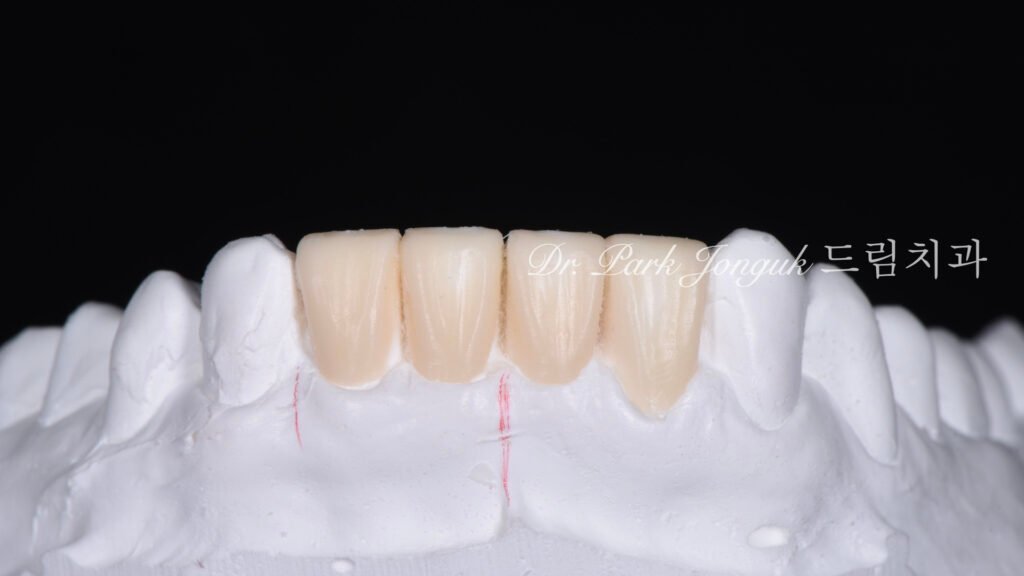

사진 3은 왁스업(Diagnostic wax-up) 정밀진단 결과입니다.

왁스업 재설계

치아의 크기(Size), 비율(Proportion), 형태(Morphology)를 완벽하게 설계했습니다. 자연스러운 형태, 밝은 색상, 투명감을 모두 계획에 반영했습니다.

환자분께서 왁스업 모형을 보시고 “이제야 자연스러운 치아를 가질 수 있겠다”며 만족을 표현하셨습니다.